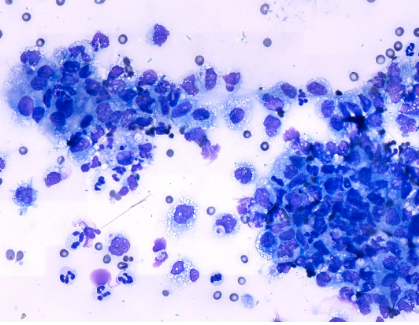

Uterine mass (Osteosarcoma, leiomyosarcoma)

유선/생식기 / 종양(간엽성) / 개

K9/ chihuahua/ 4.62kg/ 16yr/ female - 자궁 이상 및 배뇨곤란으로 내원, 초음파 리드 하에 FNA 실시